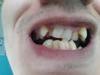

Это панорама до удаления лежачей 8-ки, но уже после удаления нижних четвёрок: